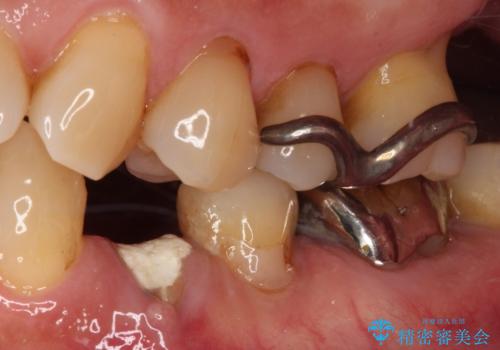

インプラント治療をお勧めしましたが、取り扱いや手入れが煩雑でも良いとのことで、可撤性義歯(入れ歯)にて補綴治療を行うこととしました。

近年の入れ歯は、クラスプという金属のバネのない、ノンクラスプデンチャーが主流となってきており、金属がほとんど使用されなくなっています。しかし、両隣の歯にぶら下がる部分には金属によるフック(レスト)を用いることが、咬み合わせや周辺の歯の安定に大きく寄与するため、今回もレストのみに金属を使用したノンクラスプデンチャーを製作しました。